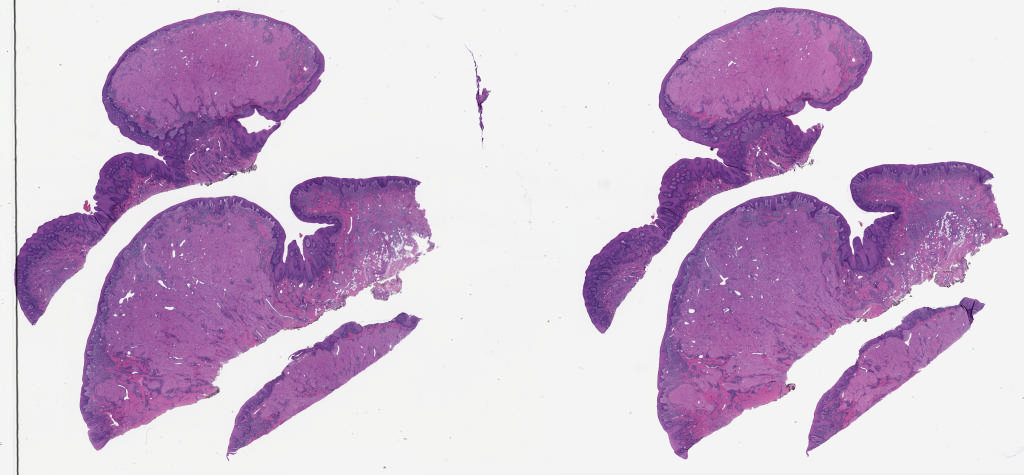

1777555.svs

1777558.svs